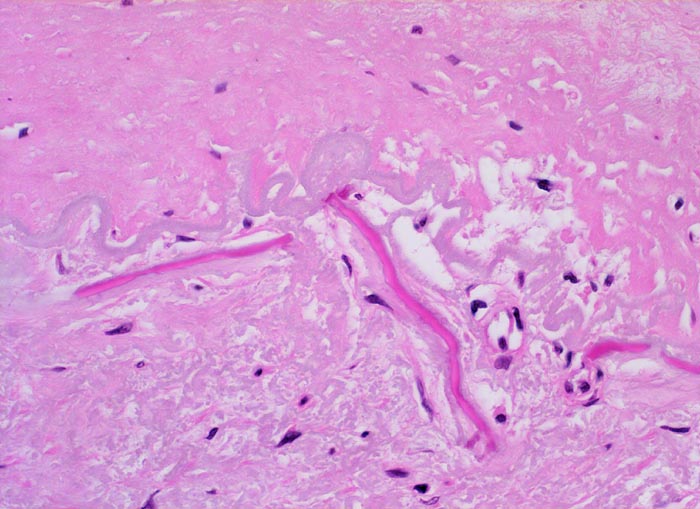

Atherosklerose

vaskulär / Durchblutungsstörung

Arteria poplitea

Aufgesplitterte Lamina elastica interna zwischen sklerosierter Intima oben im Bild und atropher Media unten im Bild. Einzelne Fasersplitter sind verkalkt.

Patient mit arterieller Hypertonie und 42 Pack Years Nikotinabusus. Klinisch PAVK IIa mit gelegentlichen leichten Schmerzen im rechten Bein nach längeren Gehstrecken.

Histologie

400

79

männlich